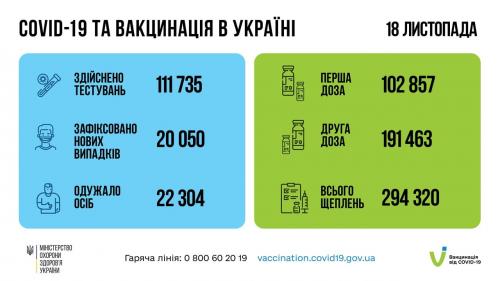

МОЗ: Уперше з початку пандемії було зроблено понад 100 тисяч ПЛР-досліджень за добу

03.02.2022 12:10